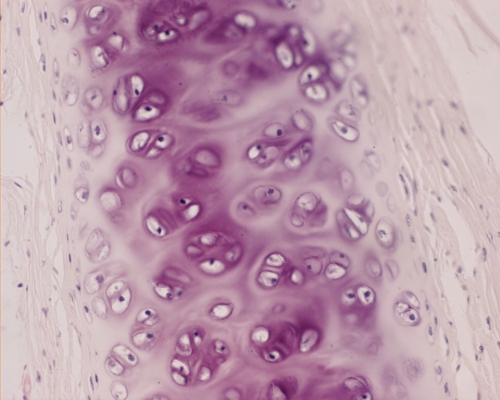

Type II collagen, a fibrillar collagen of cartilage, is composed of three identical alfa-chains called alfa-1(II).

Type III collagen is found in small amounts in many tissues and in large amounts in large blood vessels.

• Cartilage consists primarily of fibrils of type II collagen in the form of arcades that are distended by highly charged GAGs.